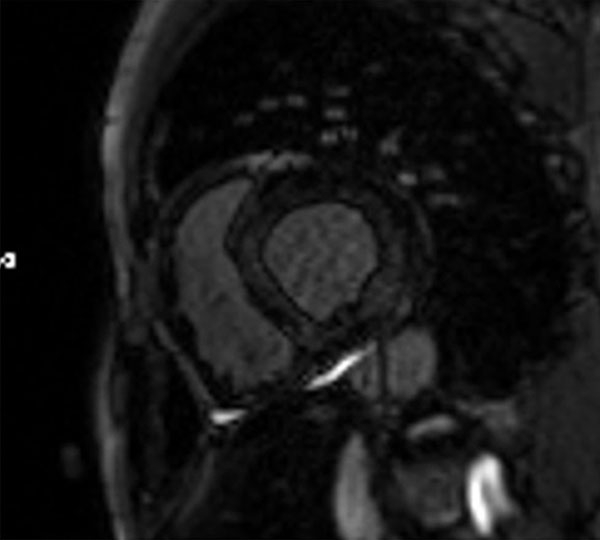

- IRM myocardique : Cardiopathie hypertrophique gauche à prédominance septale. SIV 14 mm et PPVG 12 mm ; masse 106 mg/m² non dilaté 88 mL/m². Pas d’anomalie VD

➔ Anomalie claire gadolinium patchy diffuse intra-myocardique, évoquant fibrose assez étendue diffuse non systématisée à un territoire coronaire

Figures 5 et 6 : temps de rehaussements tardifs à l’IRM

- IRM myocardique ➔ Mauvaise qualité due à l’atteinte myocardique amyloïde diffuse rendant du fait de l’absence de myocarde sain, difficile le réglage du temps d’inversion pour l’obtention de rehaussements tardifs exploitables.